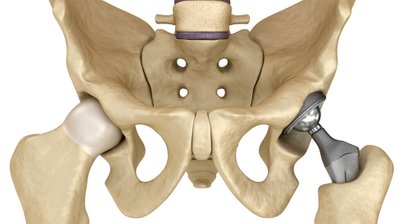

Hüft-Totalendoprothese (Hüft-TEP, Künstliches Hüftgelenk)

Hüftarthroskopie (Hüftgelenkspiegelung)

Abklärung von unklaren Hüftschmerzen